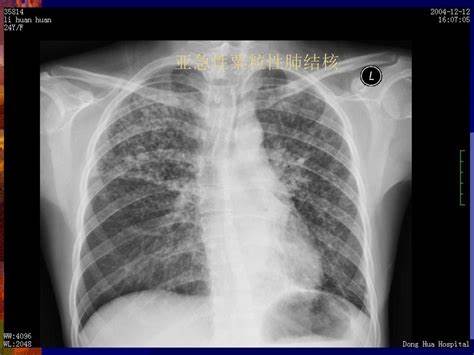

一位28岁的女性,单位体检,做了个胸片,提示左上肺有个阴影,建议进一步检查。

后来又做了个CT,提示炎性病灶,不排除肺结核。